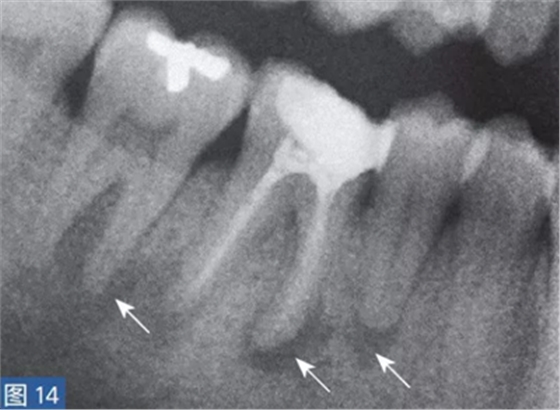

放射學(xué)檢查是診斷根尖周炎的一個(gè)重要工具。當(dāng)然,也存在多種類似于牙髓源( endodonticorigin)病變的X 線透射和阻射病變,這其中包括例如外傷、異物反應(yīng)、埋伏的遷移殘根和良性或者惡性纖維骨性腫瘤。根尖周炎也可能擴(kuò)散至鄰牙,這對(duì)應(yīng)著一個(gè)獨(dú)立的根尖周炎影像(圖14 和15)。為了獲得準(zhǔn)確的診斷,還要進(jìn)行臨床檢查,包括了解患者的癥狀及病史,并與放射學(xué)檢查結(jié)果進(jìn)行比較。

圖14:鑒別診斷。第4 象限的術(shù)前影像(取自全景片的放大圖像)?;颊吒杏X(jué)在第IV象限區(qū)的牙齒存在大范圍的不適癥狀。放射學(xué)檢查顯示, 45-47 牙齒可見(jiàn)透影區(qū)。臨床檢查,觸診和叩診45-47 牙齒疼痛明顯。46 牙齒的牙髓電活力測(cè)試為陰性,47 和45 牙齒未顯示病理特征。